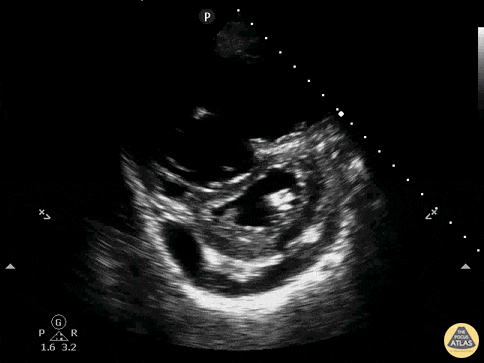

Rechtsherzbelastung

Bei einer schweren, hämodynamisch relevanten Lungenembolie lassen sich echokardiographisch Rechtsherzbelastungszeichen nachweisen. Ein klassisches Zeichen ist das sogenannte „D-Sign“. Ein Thrombus in der Lungenstrombahn führt zu einem erhöhten Druck in den Pulmonalarterien und dadurch im rechten Ventrikel. Durch den hohen Druck im rechten Ventrikel wird der linke Ventrikel komprimiert und verändert seine Form vom klassisch kreisrunden O zu einem D. Dieses Zeichen kann man in der parasternal kurzen Achse darstellen. Im 4-Kammerblick ist das rechte Herz dilatiert.

Quelle: http://www.thepocusatlas.com/right-ventricle CC BY-NC 4.0